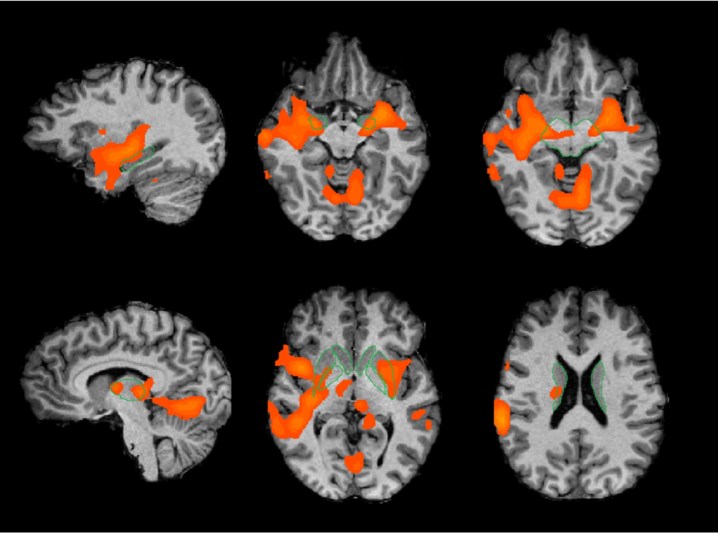

Zonas cerebrais significativamente activas nos adeptos de futebol marcadas a laranja DR

“Foi observada a activação de circuitos cerebrais de recompensa que são semelhantes aos que são activados na experiência do amor romântico”, afirma Miguel Castelo Branco, coordenador deste estudo sobre o “amor tribal” no futebol. Na investigação, explica ao PÚBLICO, foram usadas escalas validadas por psicólogos para estudar o grau do que se chama “fanatismo”. Mas, sabendo que esta palavra tem uma conotação negativa, Miguel Castelo Branco prefere chamar-lhes simplesmente “escalas de paixão pelo futebol”. Basicamente, há zonas do cérebro – como a amígdala, o núcleo accumbens e outras zonas que libertam dopamina, uma substância química do cérebro – que têm a ver com os circuitos da memória emocional e da recompensa. “São zonas que se activam tanto mais quanto mais fervoroso é o adepto”, diz Miguel Castelo Branco.

Algumas destas regiões são as mesmas que o amor romântico activa, mas não todas. “A amígdala, por exemplo, é uma das regiões que têm um padrão ligeiramente diferente. Conseguimos ver uma correlação da actividade da amígdala com a paixão clubística, mas não há achados semelhantes no amor romântico”, nota o investigador, que adianta ainda que esta área “se activa muito mais” com o estímulo do futebol. “Isto pode até, perigosamente, sugerir que estes adeptos sentem mais pelo clube do que numa situação de amor romântico”, comenta. Já no que o que se refere às regiões que libertam dopamina (como a área tegmental ventral, o putâmen e a substância negra), os sinais cerebrais são muito semelhantes aos que encontramos no “amor romântico".